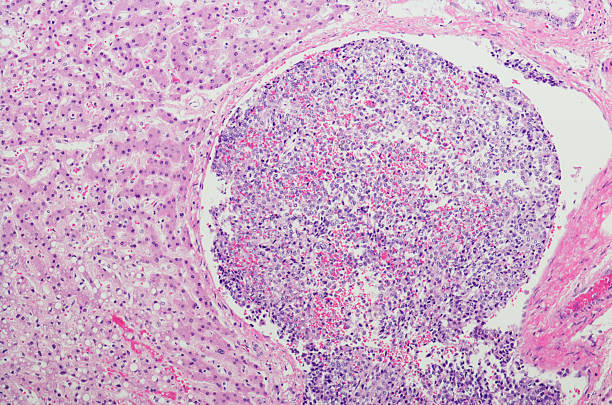

간의 역할 중 하나는 독소 제거이기 때문에, 간 기능이 감소하면 독소가 체내에 쌓일 수 있습니다. 이로 인해 복통이 발생할 수 있으며, 간이 부어오르거나 염증이 생기면서 발생하는 경우도 있습니다.